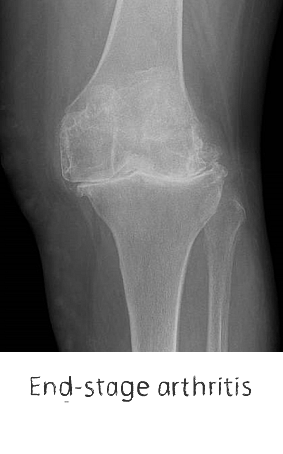

Plain film x-rays are taken to assess the joint

These are usually taken prior to your appointment. These help to confirm the diagnosis, assess the wear pattern and look for particular deformities. They can show old metalware and its position in the bone.